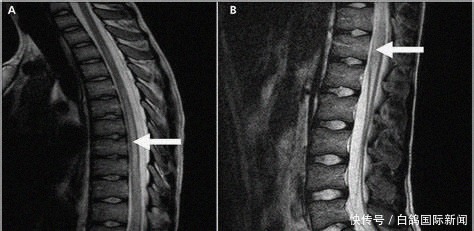

玛莉卡·马维尼(Malika Mawhinney)来自桑德兰华盛顿(Washington, Sunderland),今年11岁,有天放学后,突觉疼痛难忍,尖叫着倒下,没法动弹。母亲黛比(Debbie)赶紧送她去了医院,经诊断是横脊髓炎。这是一种非常罕见的炎症性疾病,导致病患的脊髓损伤。玛莉卡三岁起就爱打拳和体操,如今胸部以下都瘫痪,只好和这些爱好告别。

3月16日放学到家,她就对妈妈说背部疼得受不了,腿也有奇怪的感觉,之后就在地板上疼得打滚,过了一刻钟左右,她就失去知觉了。送医后,医生起初以为这是压力造成的,但最终却发现这是炎症导致的。

做了几场手术后,小玛莉卡胸部以下还是没能恢复知觉,尽管不忍心,医生还是告知了黛比,小姑娘以后恢复知觉的可能性“微乎其微”。黛比说,做了很多检查,还是不知道病因,还听说小孩患这种病的机率不到百万分之一。